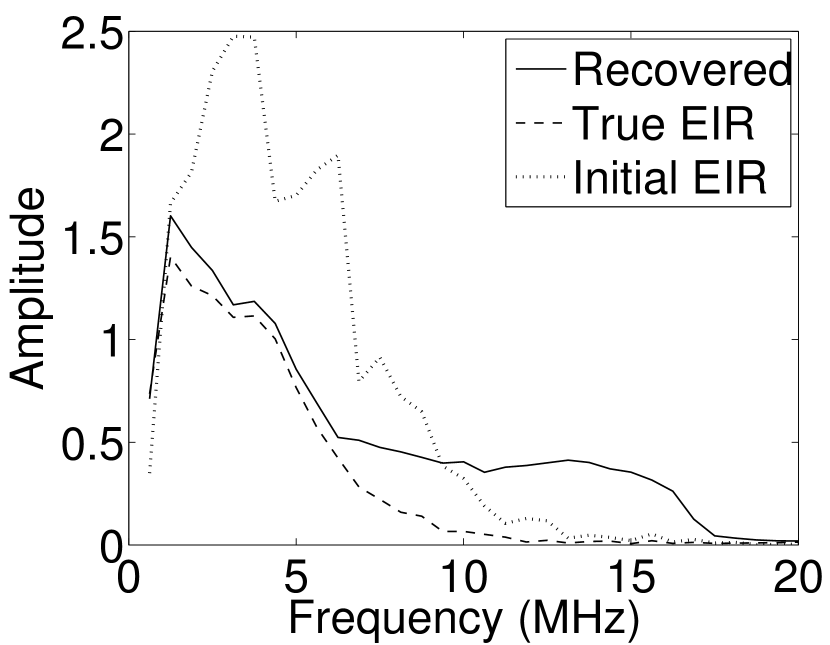

Images reconstructed by use of the VP algorithm with different values of the regularization parameter values are shown in Figure 8. The recovered EIRs and their corresponding Fourier spectra are shown in Figures 9 and 10, respectively. The RMSE values are computed and displayed together with the corresponding images. As expected, the images reconstructed with smaller values of contain higher noise levels, while images using larger possess a reduced noise level. However, larger values of also caused artifacts in the reconstructed images. The same observation can be made for the effect of the regularization parameter on the recovered EIR. One also observes that the reconstructed images and EIRs depend continuously on the regularization parameters and , i.e. small changes in the regularization parameters cause minor changes in the reconstructed images and EIRs.

VI Experimental validation